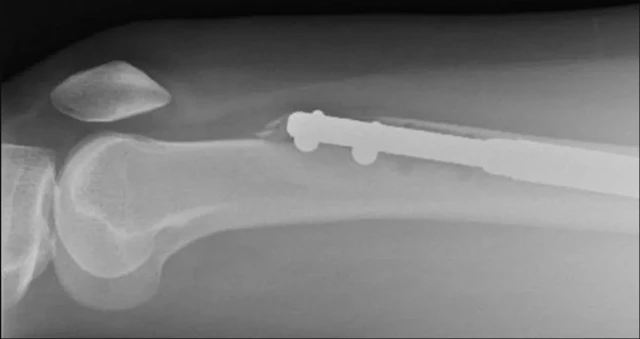

Eekannaa to wa ninu ẹsẹ osi Elaine Foo ti kan, eyi si ni egungun to lagbara julọ ninu egungun ara eniyan

Eekannaa to wa ninu ẹsẹ osi rẹ ti kan, eyi si ni egungun to lagbara julọ ninu egungun ara eniyan.

Ni iru igbesẹ bayii, o ṣe dandan lati la irora kọja. Lasiko iṣẹ abẹ naa, egungun naa kan si meji, wọn si fi irin sii lati fi ṣe iranwọ ninu.

Diẹdiẹ ni irin naa n ga lati le jẹ ko gun, yoo si wa ti egungun naa sọtọọtọ. Igbesẹ yii ni lati jẹ ki eeyan ga bo ṣe fẹ. Awọn egungun to kan naa yoo jinna pada lati di alafo to wa nibẹ.